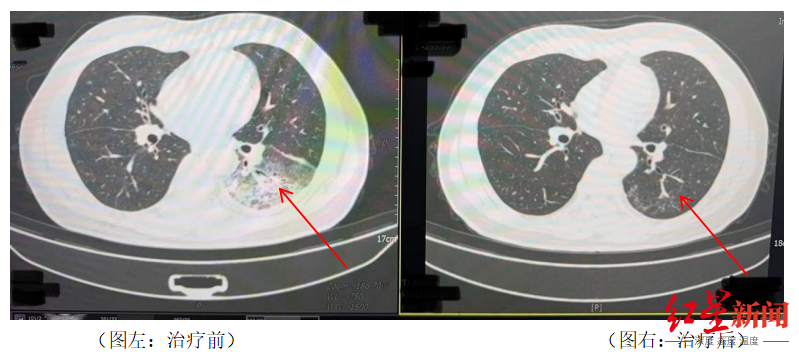

13 吹了3天空调,一男子左肺“白”了一半!专家紧急提醒

近日,四川成都气温逐步升高,市民李先生在开启尘封一年的空调后,竟意外患上了严重的军团菌肺炎,左肺接近“白”了一半。【点击查看详情】